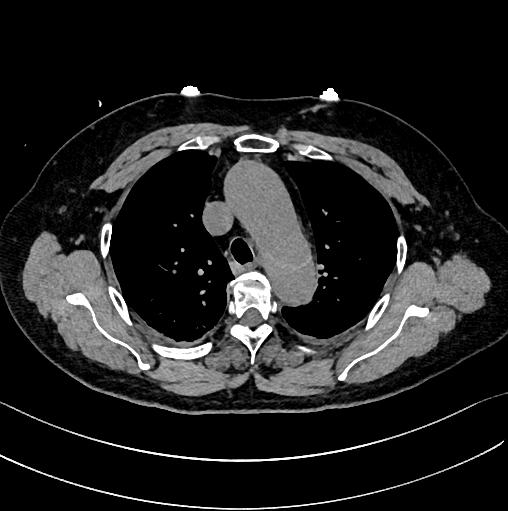

查到一篇文献,作者虽然用箭头标记了,并且是增强CT,但是鲁迅说:我大约肯定没有看出来,这是主动脉夹层!

图21